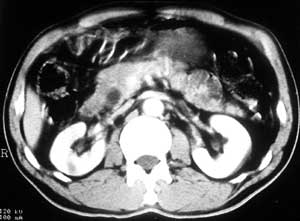

患者,男,57岁,梗阻性黄疸10余天。

这个病例胰头无明显增大,胆总管扩张明显而肝内胆管扩张更不明显,病程较短,

注意到十二指肠乳头明显突出,但尚光滑。分析以下可能性:

1、十二指肠乳头本身的病变,如乳头炎症;

2、急性乳头水肿,胆总管下端结石排石后乳头水肿;

3、壶腹部胆总管下端肿瘤累及十二指肠乳头。

十二指肠乳头粘膜慢性非特异性炎症